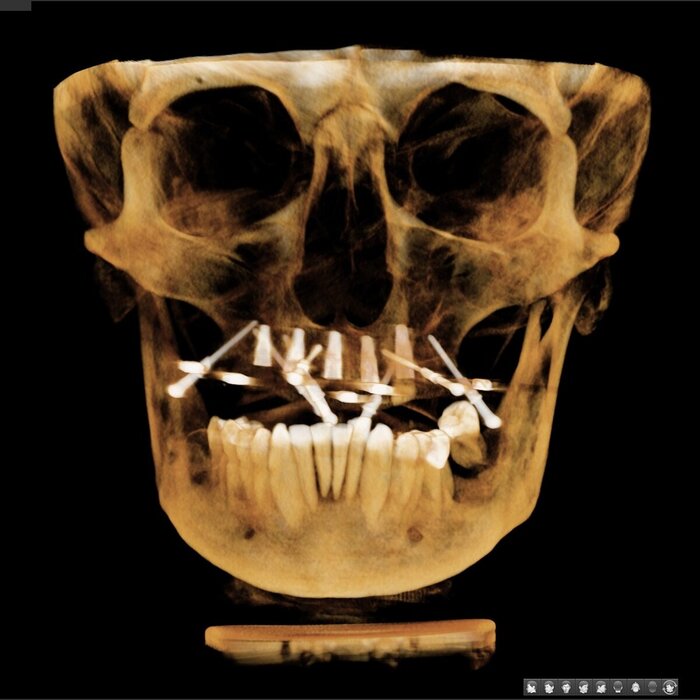

Как же всё-таки у нас происходит это мероприятие? Так как мы вмешиваемся в другую область нашего тела, то стоматолог должен быть хоть немного лором. Разумеется, всё начинается с обследования, которое включает в себя трехмерный снимок, который, в идеале должен захватывать не только зубы и область наращивания, но и носовые ходы с устьями гайморовых пазух и прочими загогулинами, то есть, так называемый остиомеатальный комплекс.

Поэтому кастрированный снимок, где видна только область установки будущего имплантата не прокатит. Тем более в центрах КТ такой снимок стоит дороже классической КТ рублей на 200. И стоит ли экономить?

Анализируя снимок, мы должны принять решение о том можно ли делать синус-лифтинг или отправить его на консультацию к лору. Если всё хорошо, то планируем операцию.

Выглядит это так. Это, кстати, один из моих первых открытых синус-лифтингов, когда я только закончил ординатуру. Сейчас я сделал бы это по-другому. Кости хоть и 4 мм, но она была достаточно мягкая и я был не уверен, что установлю имплантаты сразу.